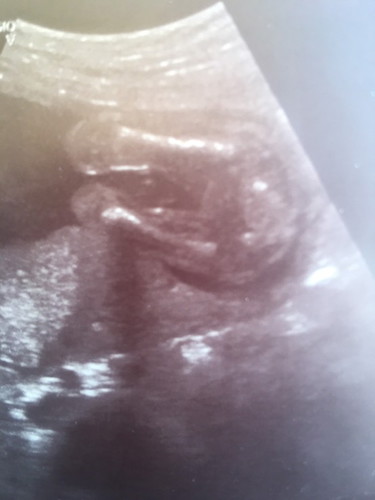

ช่วยดูหน่อยนะคะว่าน้องเป็น ญ/ช ค่ะ

แบบนี้หญิงหรือชาย

เหมือนหญิงเลยค่ะ ไม่มีจรวด

ผู้หญิงค่ะจู๋ไม่โผล่5555